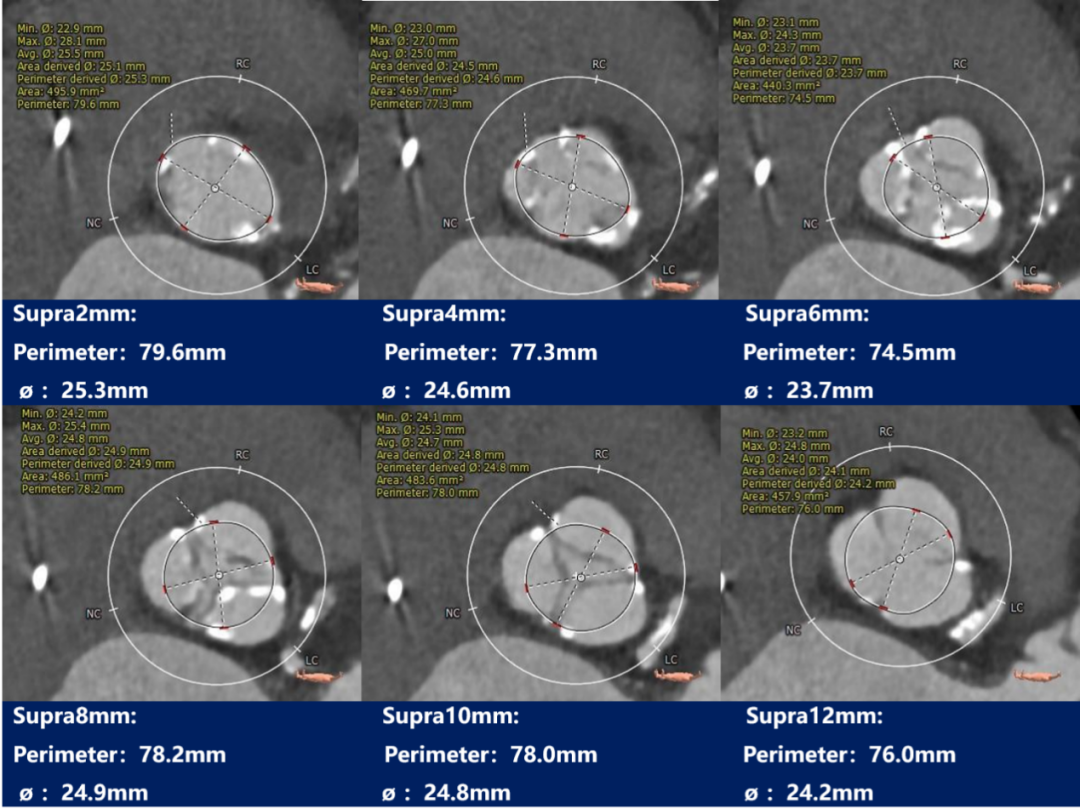

瓣上测量

瓣上测量:瓣叶重度钙化,钙化分布稍欠均匀,钙化主要分布在瓣叶边缘,锚定力量主要来源于瓣上2-8mm。